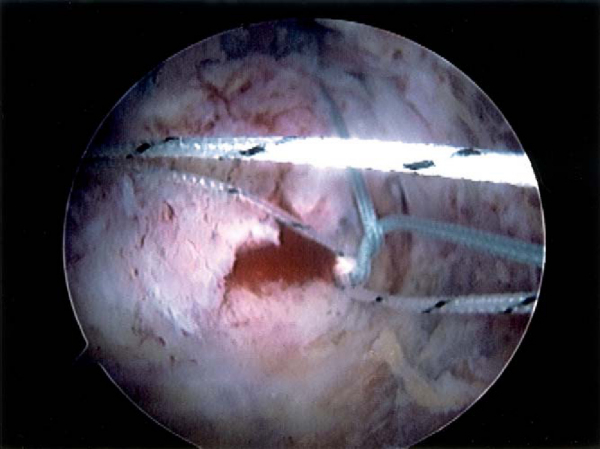

A new implant has been developed to facilitate placement of compression sutures and to reduce knot tying. For the PushLock (Arthrex, Naples, Fla) device, medial suture anchor placement and suture passing are performed as previously described for the double-row repair technique. A hole is then punched at the intended site for the lateral implant, just lateral to the lateral edge of the tuberosity. The medial sutures to be used for compression (one suture from the anterior medial anchor and one suture from the posterior medial anchor) are then passed through the eyelet of the implant outside the cannula (

Fig. 17-16

). Manual tension is applied to the suture bridge sutures as they are delivered into the tunnel to achieve the desired compression (

Fig. 17-17

). The implant is advanced over the inserter and captures the eyelet, which fixes the sutures in place and eliminates the need for knot tying. The sutures are then cut. Cruciate suture configurations can be made with a second PushLock anchor to further enhance the repair (

Fig. 17-18

).

Figure 17-19

demonstrates a case example of a crescent-shaped tear repaired with a four–suture bridge technique.